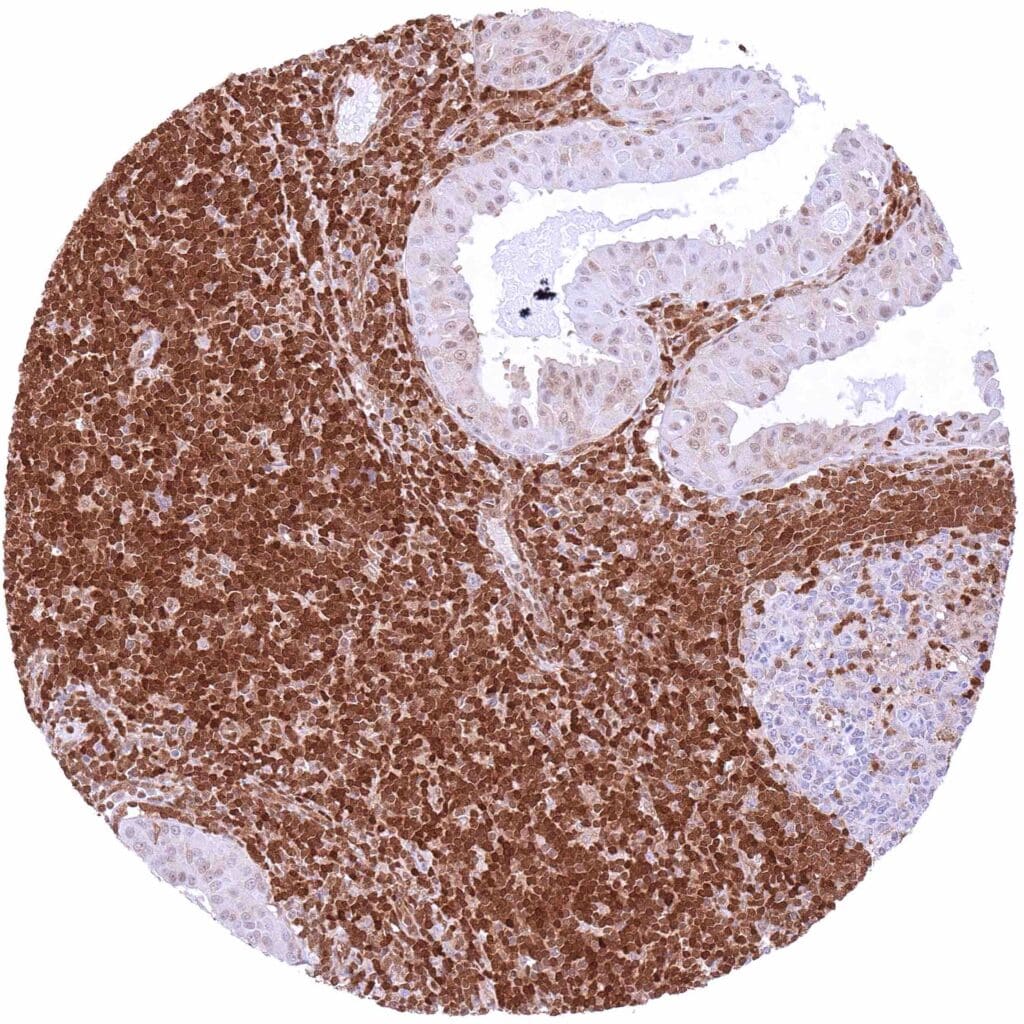

Lymph node – B-CLL with intense nuclear and cytoplasmic p27 positivity of all tumor cells.